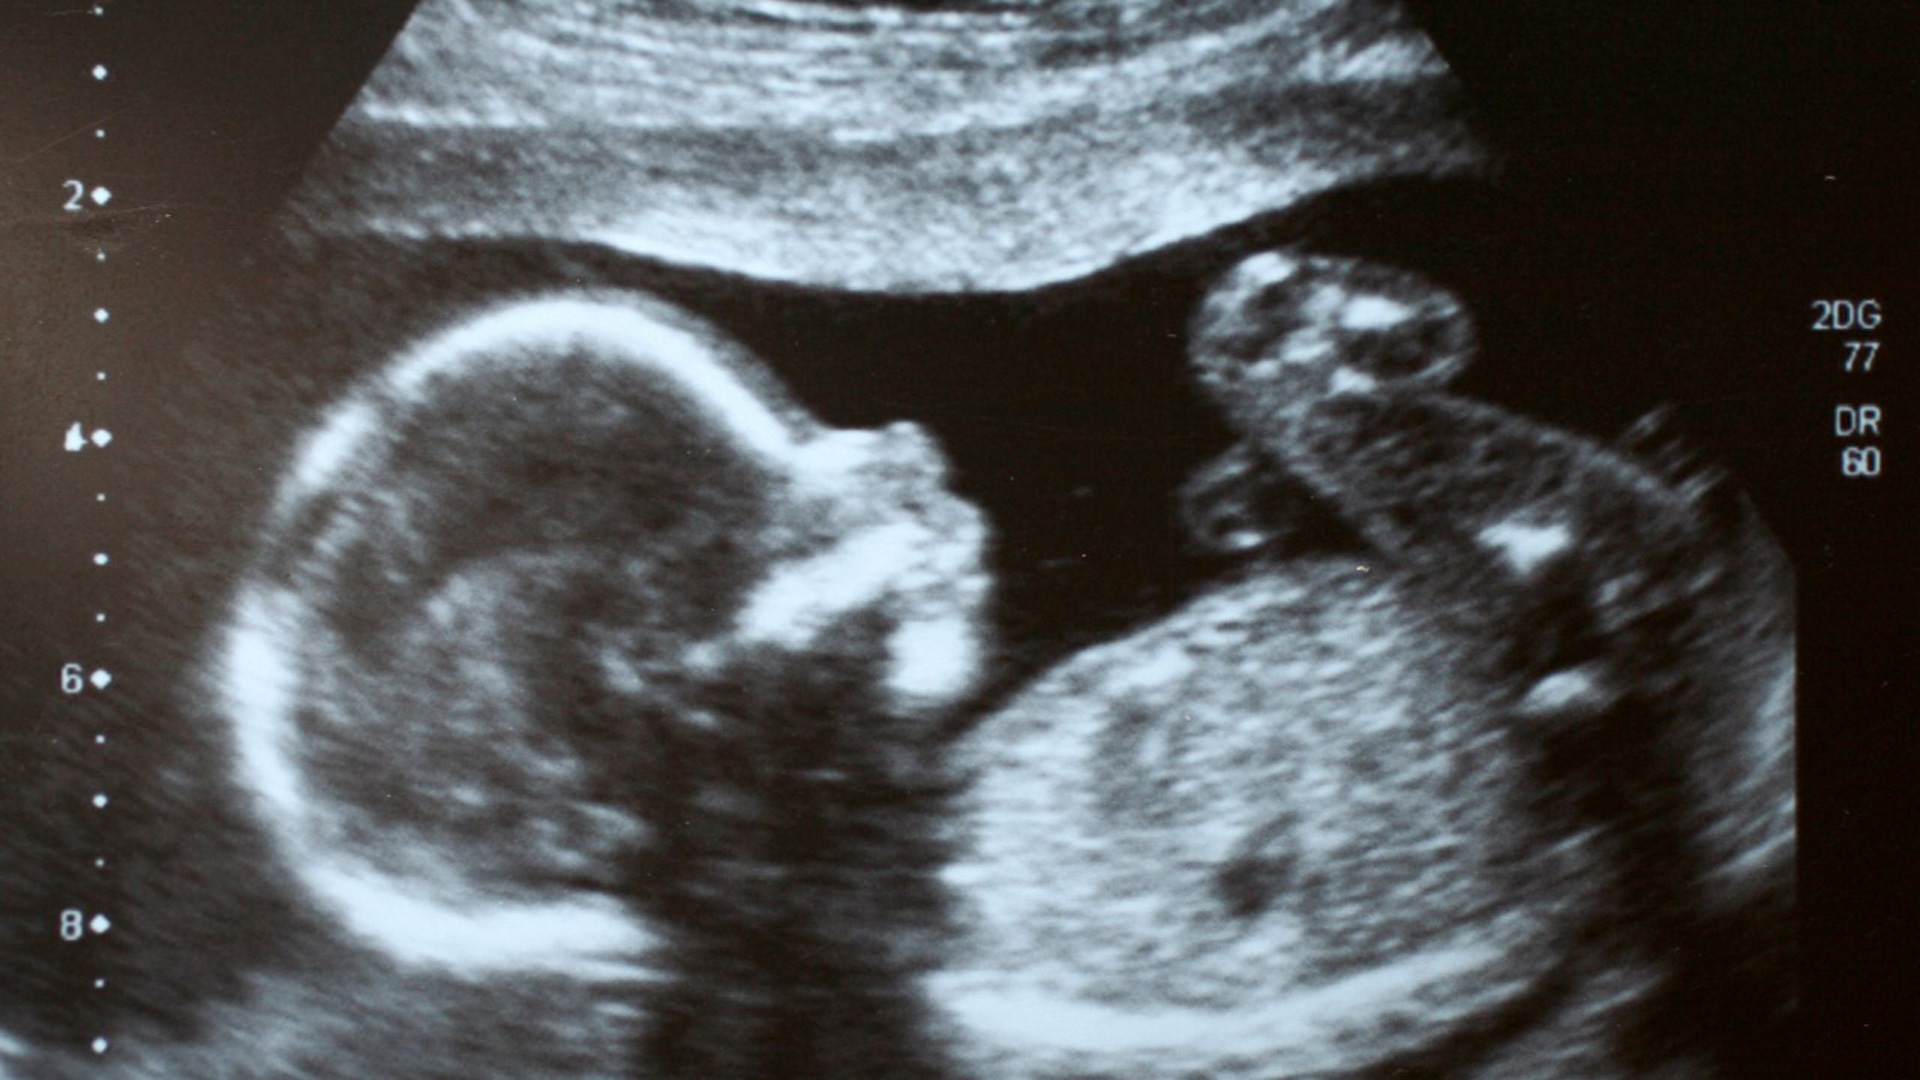

El duelo de los padres que no llegan a ver nacer a su hijo o que lo pierden de recién nacido es un tema tabú. Se evita hablar de él y a menudo se le resta importancia. Pero en España cada año son unas 2.500 familias las que pasan por ese trance y la mayoría de las veces con escasa ayuda.

Un equipo de Informe Semanal ha hablado sobre cómo se gestionan y se deben gestionar esos duelos con médicos, enfermeros, psicólogos, y también con familias que han vivido esa situación. Ana y Juan han pasado por ella dos veces. Primero, perdieron a su hija Mariona cuando solo tenía dos meses y medio, y luego sufrieron un aborto a las 8 semanas de embarazo.

Algunos hospitales, como el Clínic de Barcelona, tiene su propia hoja de ruta, pero no es lo que sucede con la mayoría. La petición de que se cree un protocolo cómun a nivel nacional que ayude al personal sanitario a abordar este tipo de muertes es compartida también por los profesionales de la salud. Es importante cuidar los detalles cuando se comunica a una familia que han tenido una pérdida gestacional.

La invisibilidad del duelo perinatal se manifiesta también en el hecho de que las mujeres que sufren un aborto espontáneo antes de los 180 días de gestación no tienen reconocido derecho a baja.